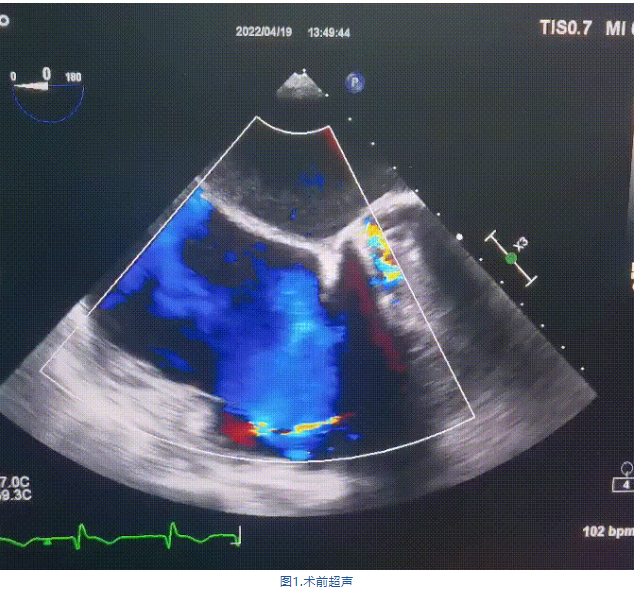

術(shù)前超聲提示:

1.右心、左房明顯增大;

2.二尖瓣人工機(jī)械瓣功能正常,無瓣周漏;

3.三尖瓣環(huán)巨大擴(kuò)張,收縮期瓣葉對合不攏,收縮期三尖瓣房側(cè)見大量反流信號,反流面積15-20cm²,TRVmax:240cm/s,跨瓣壓差:23 mmHg。